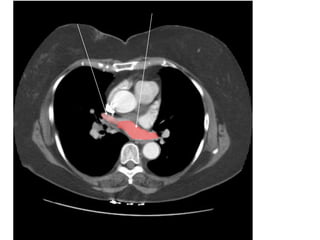

VỠ LOÉT ĐỘNG MẠCH CHỦ NGỰC

-> MÁU XOANG NGỰC (T)

VỠ LOÉT ĐỘNGMẠCH CHỦ NGỰC -> MÁU XOANG NGỰC (T)